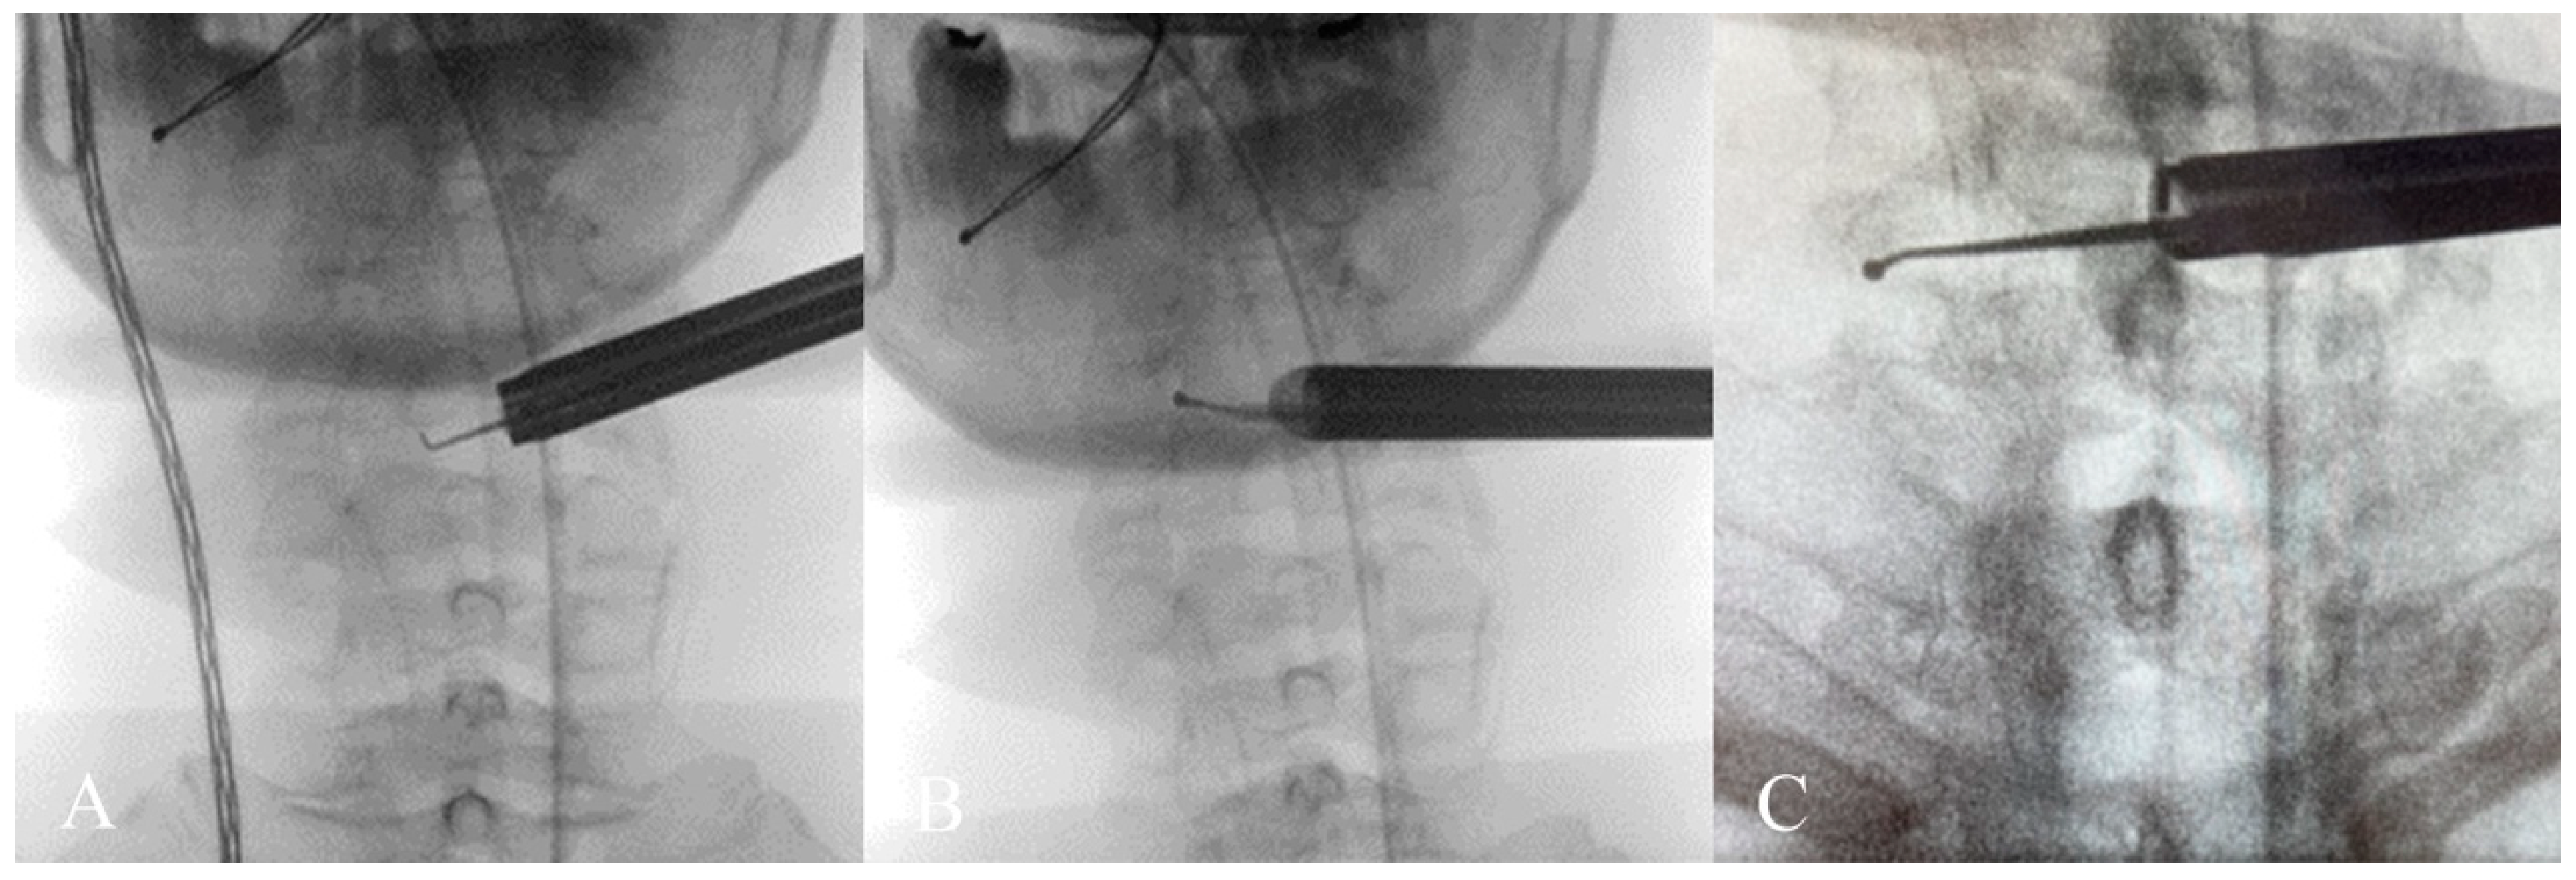

The patient underwent C3-C6 CE-ULFBD (Figure 11) in October 2022, with a focus on a thorough bilateral foraminotomy at C5-6 to address the radiculopathy in both upper limbs. The surgery lasted 106 min with a blood loss of 5cc. The patient experienced immediate postoperative pain relief and was discharged the following day to continue recovery at home. The neck pain Visual Analogue Scale (VAS) score improved from 8 preoperatively to 2 postoperatively, and the arm pain VAS score decreased from 8 preoperatively to 1 postoperatively, with both becoming pain-free at six months. Gait instability gradually improved, and the modified Japanese Orthopedic Association (mJOA) score returned to 16 at the one-year follow-up. Figure 12 shows the preoperative and postoperative MRI images.

Figure 11. (AC) depict intraoperative X-rays during contralateral laminar and foraminotomy decompression, demonstrating the extension of the spinal endoscopic instruments to the far edge of the contralateral foramen.